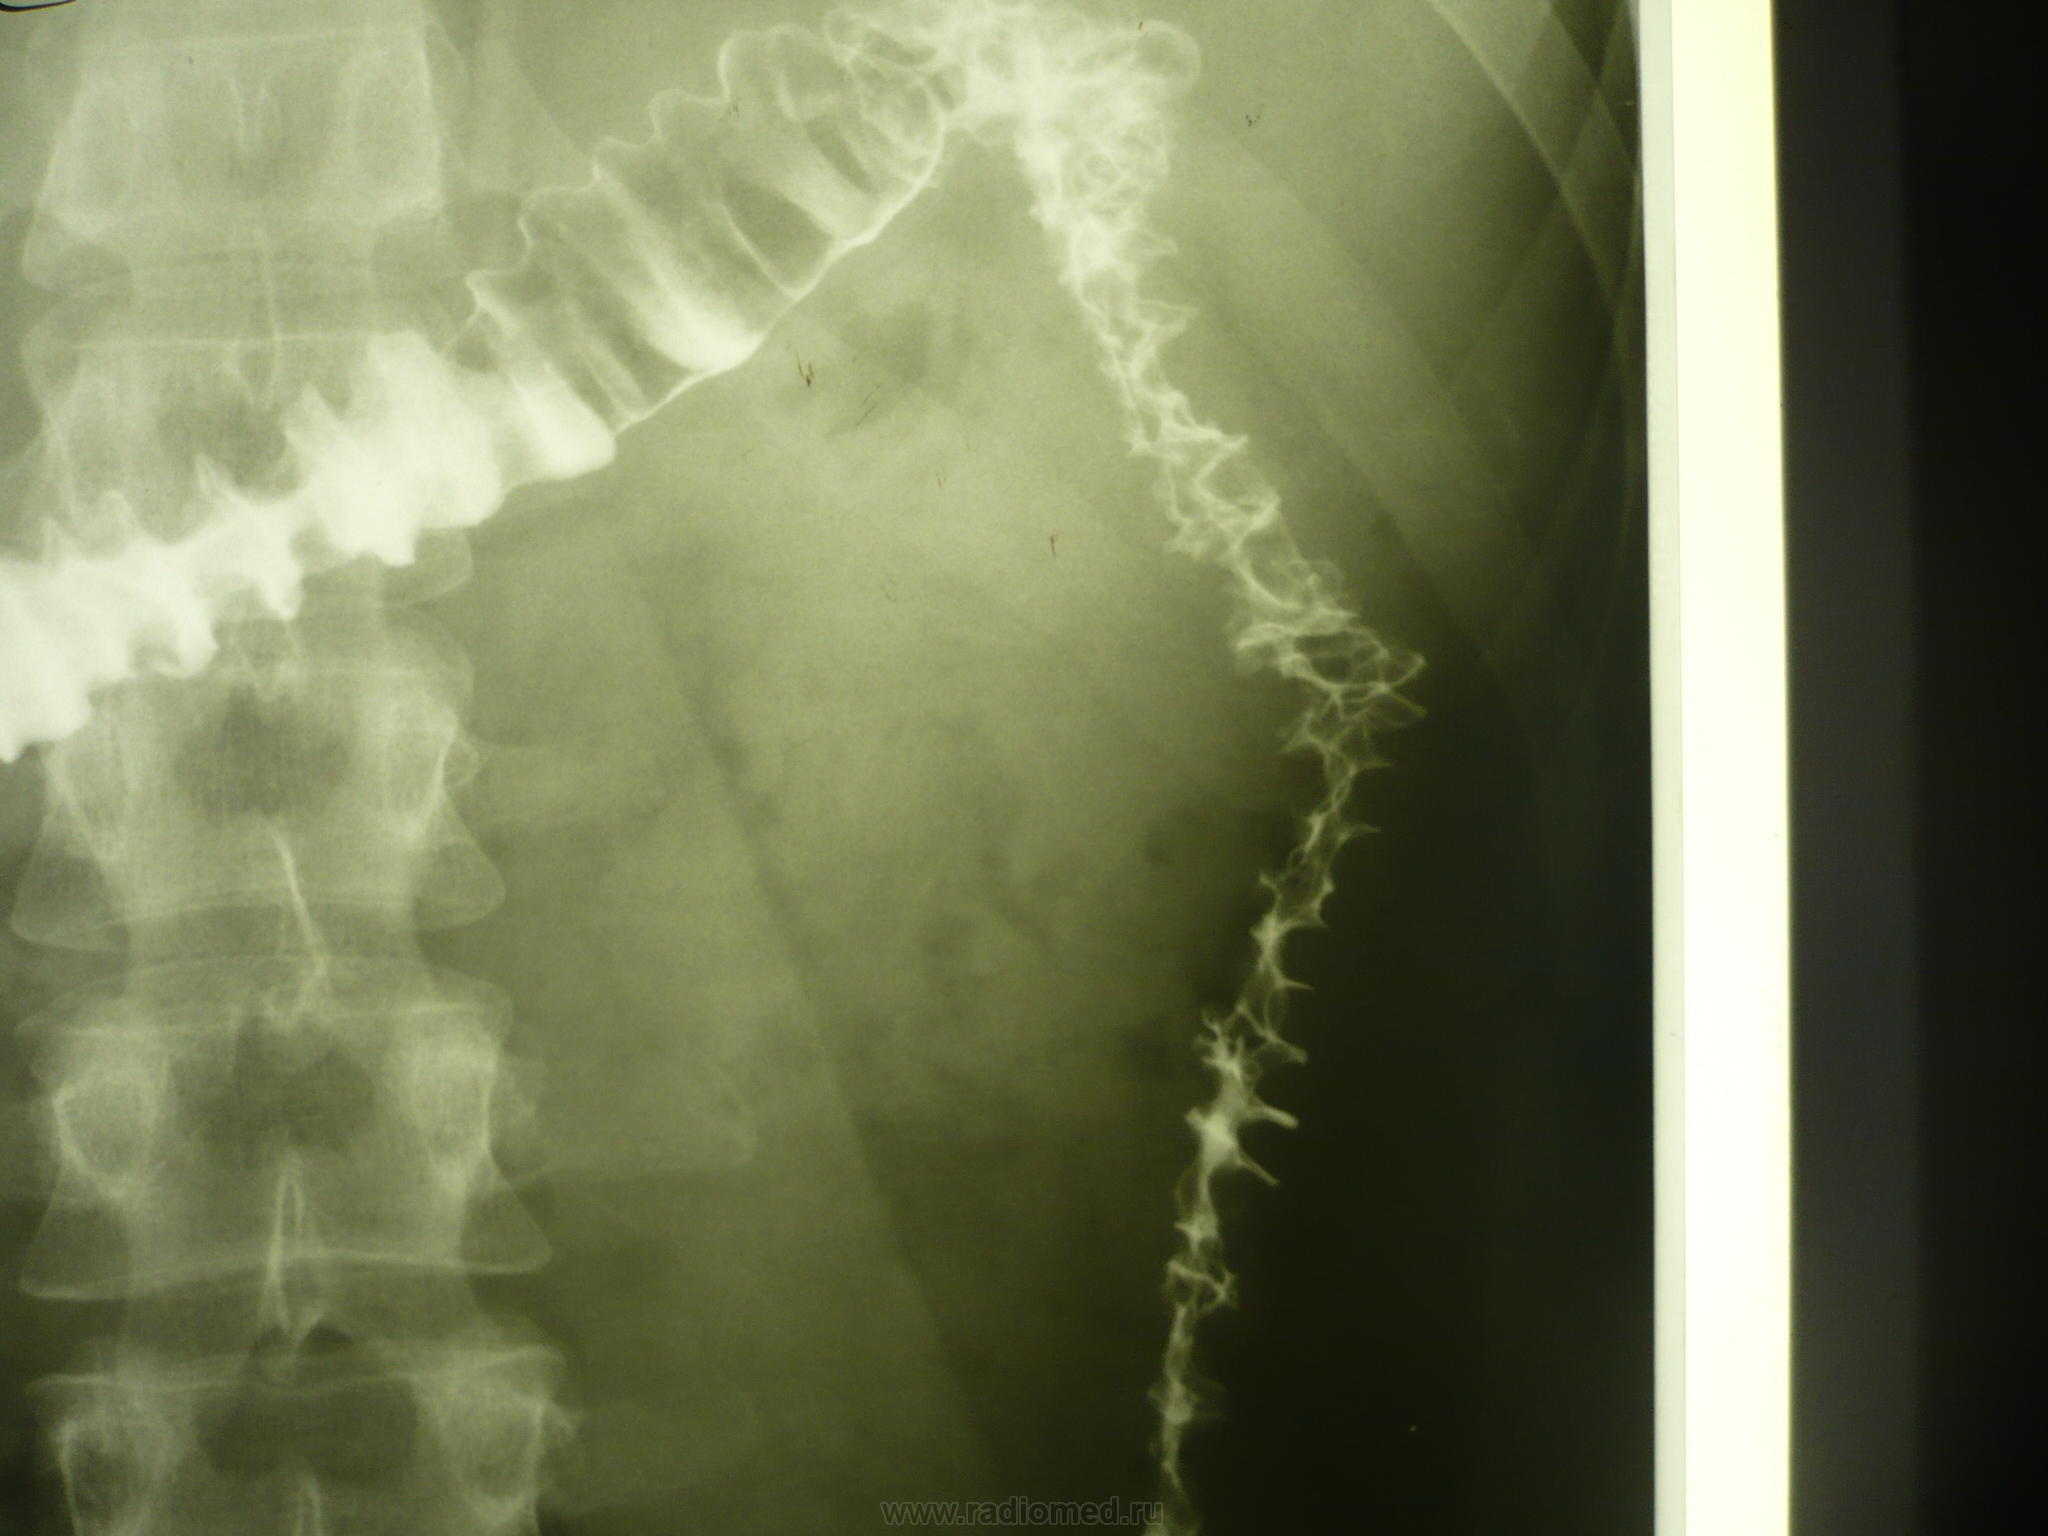

М., 26 лет. Жалобы на боли в обл живота в течение года. Есть что-то нехорошее, или норма?

Соглашаясь, в целом, с уважаемым Анатолием Владимировичем, тем не менее, обратил бы ваше внимание на нессиметричность гаустр нисходящей ободочной кишки, неравномерность, зубчастость (при тугом выполнении)...все это не в пользу нормы, даже при вариабельности рельефа, т.е. - явления колита присутствуют. Такое вот мое мнение.

Скорее - норма - рельеф толстой кишки вариабилен, ирригоскопия крайне афизиологическое исследование.

Другая особенность - у пациента кишка тесно прилежит к селезенке и огибает все ее формы - возможно там имеются спайки. Это состояние с высокой фиксацией и спайками в области селезеночного изгиба - называют синдром или болезнью Пайра.

Коллеги рентгенологи, не кажется ли Вам, что слева в нисходящей части в разное время имеется одно и то же очень короткое сужение, или перегиб. Вероятно не следует ставить диагноз по снимкам не видя динамики заполнения.

Если дискутировать о сфинктерах - то это спазмированный сфинктер.

Если это постоянный спазм - надо делать биопсию при колоноскопии.